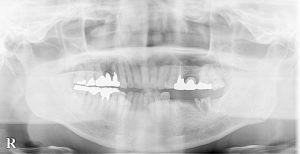

●骨隆起

●臼歯の歯冠、歯根の破折、隣接面カリエス

●咬合面 切端の咬耗

写真は、いずれもTCH(tooth contacting habit、上下歯列接触癖)の方の特徴ですが、40歳代くらいになると奥歯からトラブルが出てきて、喪失していきます。

歯の喪失したところにブリッジ、義歯などの補綴。

インプラント治療をしてもトラブル続きで、患者さん本人も担当歯科医師も悩まし続けます。